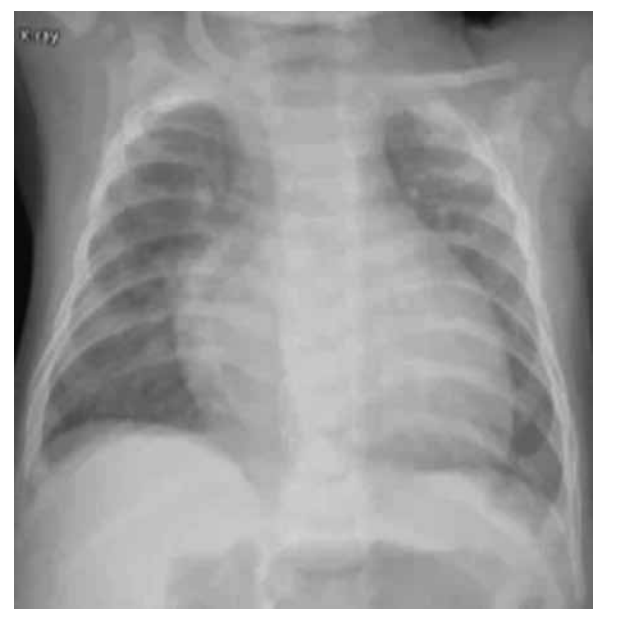

Uma lactente de 5 meses, do sexo feminino, foi internada na UTI com uma hipótese diagnóstica de choque séptico. Apresenta síndrome de Down e defeito do septo atrioventricular com moderada repercussão. Está em uso de carvedilol, captopril e furosemida. Aguarda agendamento cirúrgico para correção total da cardiopatia. Vem apresentando febre, há três dias, de até 38 ºC. Realizou-se raio-X do tórax (figura a seguir), administrou-se a primeira dose de ceftriaxona, e a paciente foi encaminhada para a UTI.

(Arquivo pessoal; imagem usada com autorização)

Ao exame físico, encontra-se sonolenta, mas abre os olhos ao chamado. Frequência respiratória: 65; batimento de aleta nasal; retração intercostal e subdiafragmática; saturação de 91% com máscara não reinalante 15 L/minuto; FC: 175; tempo de enchimento capilar de 5 segundos; pressão arterial: 75 x 55. Ausculta cardíaca: bulhas rítmicas normofonéticas com sopro sistólico +++. Ausculta pulmonar: murmúrio vesicular presente bilateralmente com estertoração crepitante bilateral nas bases. Abdome: globoso, flácido, doloroso à palpação do hipocôndrio direito, com fígado palpável a 4 cm do rebordo costal direito.